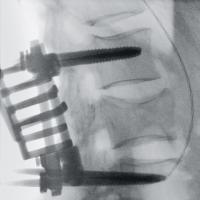

手術室内で移動式のX線装置を使用して行う撮影です。

直接目視できない部分をX線画像でリアルタイムに見られるため、より安全に手術を行うサポートができます。

一例として、金属のボルトを骨内に挿入する際に、位置や角度、深さを様々な方向から観察できるほか、装置を回転させて撮影することで、CT画像のような自由な断面像を得ることも可能です。